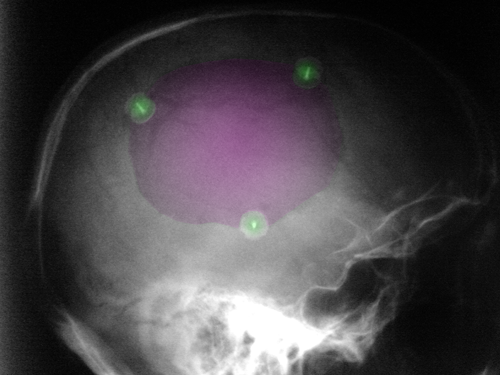

Κρανιοπλαστική (μώβ). 3 στηρικτικά κλιπ τιτανίου με πράσινο.